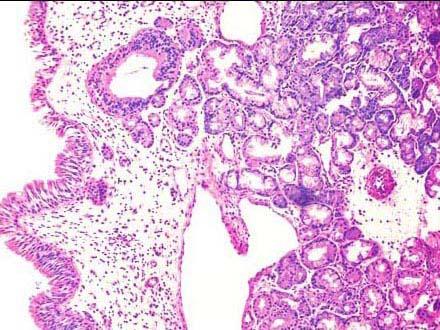

问题 患者,男,27岁,鼻塞、流涕、头痛、咽干一年,该症状在冬季比较明显,鼻腔镜下黏膜粗糙,取活检镜下如图所示,该患者的可能的疾病是 ( )

选项 A.急性鼻炎 B.慢性鼻炎 C.慢性萎缩性鼻炎 D.干酪样鼻炎 E.鼻咽癌

答案 B